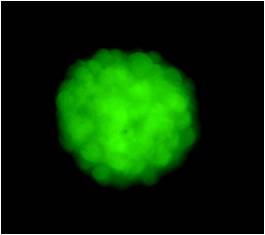

鏡下的神經(jīng)干細胞分裂成神經(jīng)球。在胚胎大腦的發(fā)育中,越早期的胎腦,其神經(jīng)干細胞比率越高,用直接分離的自然流產(chǎn)的胚胎新鮮腦組織可以在體外增殖形成神經(jīng)球